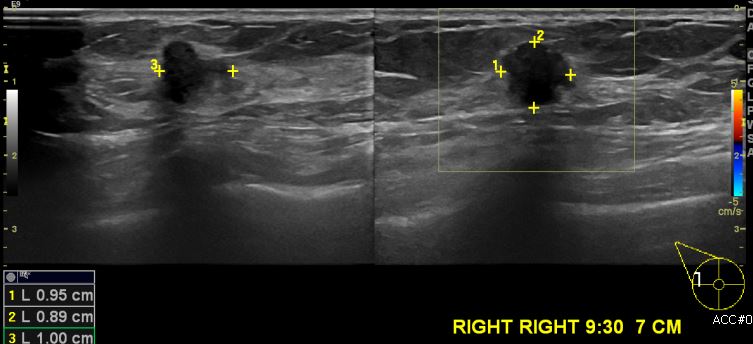

상기환자 건강검진상 이상 소견으로 내원하신 60대 여성 분으로 우측 유방 9시 30분

방향에서 7cm 떨어진 거리의 혹 조직검사 시행하여 우측 침윤성 유관암 진단 되었습니다.